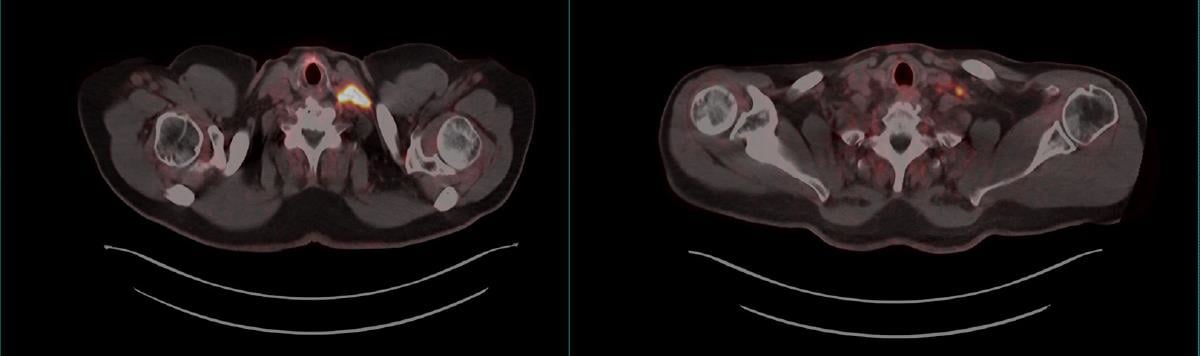

PET er bildediagnostikk som viser hvordan radioaktive legemidler (PET-radiofarmaka) fordeler seg i kroppen. Det utvikles stadig nye PET-radiofarmaka som gjør oss i stand til å avdekke sykdom mer presist og mer spesifikt. Teranostikk er et behandlingskonsept hvor den bildegivende radioaktiviteten ved PET erstattes med en radioaktiv «sprengladning» som medfører celledød. Ett eksempel på PET og tilhørende teranostikk er PET-avbildning med 68Ga-PSMA, som fester seg til PSMA-reseptorer som utrykkes på kreftceller fra prostata, med påfølgende behandling med 177Lu-PSMA hvor 177Lu er en radioaktiv «sprengladning» og medfører celledød til de celler som avbildes ved PET.

PET-avbildning med 68Ga-PSMA avdekker prostatakreft. Venstre bilde: Lysende område i halsregion hvor 68Ga-PSMA har bundet seg til PSMA-reseptorer på kreftceller fra metastaserende prostatekreft. Høyre bilde: Pasienten har gjennomgått teranostisk behandling (177Lu-PSMA) og ny PET-avbildning viser at tumor er betydelig redusert.

Kilde: Universitetssykehuset Nord-Norge HF